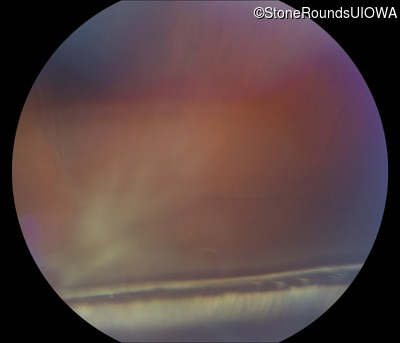

B-Scan Ultrasonography - Right - 20/300 sc

Exemplar